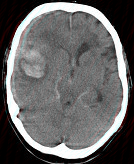

- 单项选择题女,79岁, 突发神志不清,请结合影像图像判断其最可能的诊断 ( )

A、脑转移瘤出血

B、脑脓肿

C、脑梗死

D、右大脑中动脉破裂出血

E、脑膜炎